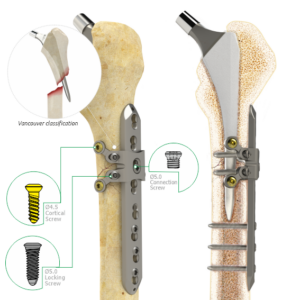

Locking Proximal Lateral Femoral Head Plates

-